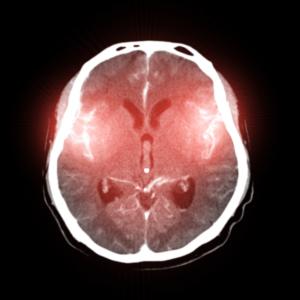

В зависимост от сериозността на случая, човек може да срещне трудност при разпознаването на познати лица, различаването на непознати или различаването на лица от предмети. Прозопагнозия обикновено настъпва в резултат на инсулт, но около 2,5% от пациентите се раждат с това състояние.

Тези хора страдат от хемианопсия – заболяване, което настъпва в резултат на увреждане на едното мозъчно полукълбо и кара човек да губи представа за съществуването на половината заобикалящо го пространство. Пациентите не могат да виждат или обработват информация, получена от едната страната на тялото или средата (обикновено противоположната на засегнатото полукълбо страна).